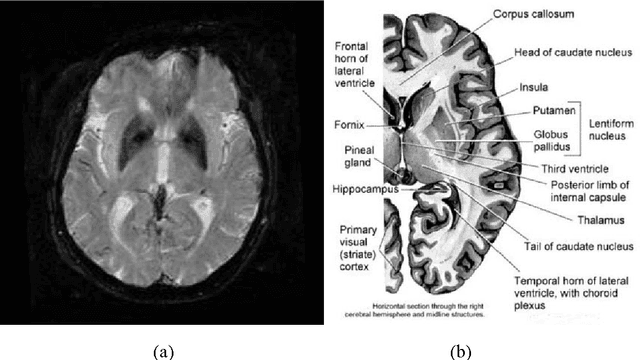

Abstract:Accumulating evidence has shown that iron is involved in the mechanism underlying many neurodegenerative diseases, such as Alzheimer's disease, Parkinson's disease and Huntington's disease. Abnormal (higher) iron accumulation has been detected in the brains of most neurodegenerative patients, especially in the basal ganglia region. Presence of iron leads to changes in MR signal in both magnitude and phase. Accordingly, tissues with high iron concentration appear hypo-intense (darker than usual) in MR contrasts. In this report, we proposed an improved binary hypointensity description and a novel nonbinary hypointensity description based on principle components analysis. Moreover, Kendall's rank correlation coefficient was used to compare the complementary and redundant information provided by the two methods in order to better understand the individual descriptions of iron accumulation in the brain.